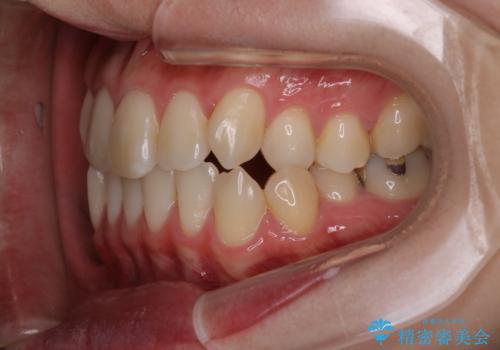

【インビザライン】歯の本数少ないのにがたつきがある セラミックインレー

- 右上2番が欠損しており、歯並びをバランスよくしたいということで来院されました。

IPR、歯列弓拡大、ゴム掛けを行い歯並びを整える治療計画を立てました。

右上2番が欠損しているため、見た目と噛み合わせの両方のバランスを整えるために経過を追いながら必要な部位にゴム掛けをしました。

また矯正後、患者様の希望で

メタルインレーをセラミックインレーにやりかえさせていただき、さらに綺麗に仕上がりました。